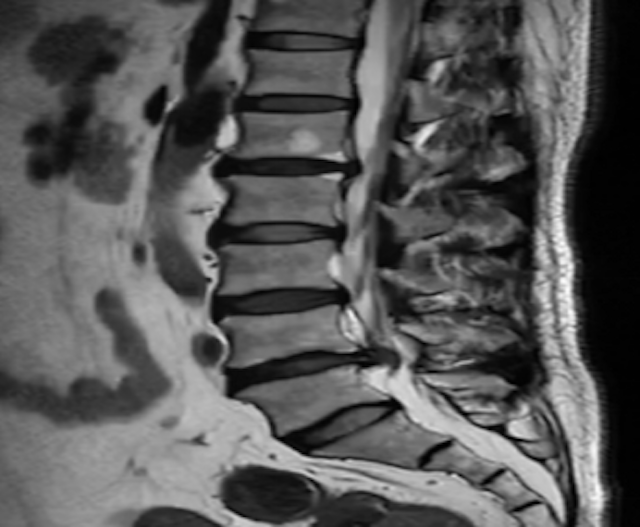

患者的家属经多方打听,目前有郑大一附院脊柱外科张华峰博士在哈密市中心医院开展援疆工作,主要从事脊柱侧弯及脊柱微创手术,手术效果都非常好,一个多月前,来我院脊柱外科门诊就诊,查MRI显示腰4/5椎间盘突出,椎管狭窄,需行微创手术治疗。

患者入院后,完善相关术前检查,援疆专家张华峰博士和我院脊柱外科张积利主任、柳廷坤副主任团队一起进行了术前讨论,患者椎间盘突出,腰椎管狭窄的诊断明确,经保守治疗无效,手术指征明确。考虑患者年轻相对较轻,无脊柱不稳等表现,适合行UBE椎管减压椎间盘切除术。